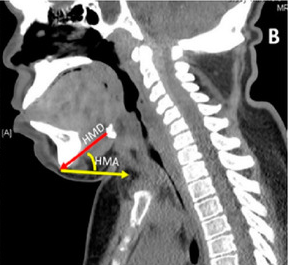

The thyromental distance (TMD), which is precisely measured with a ruler, is the distance when the head is completely extended, between the chin (mentum) and the top of the thyroid cartilage notch. The following points help in evaluating the thyromental distance:

The thyromental distance is determined with the patient’s neck stretched and mouth closed. The distance is then measured using a ruler or another type of measuring equipment, beginning at the upper border of the thyroid cartilage and continuing down to the very tip of the chin.